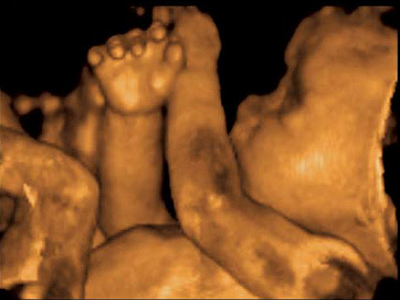

Imagen 2o. Trimestre

Ultrasonido estructural de 2do. trimestre

Se trata de un estudio visual minucioso y detallado en el cual se evalúan y miden todas las estructuras fetales.